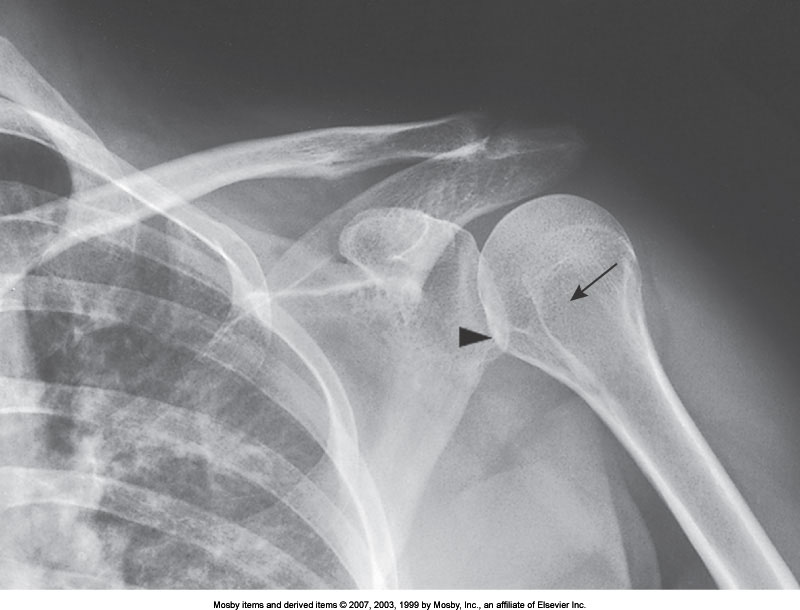

AP Shoulder (Internal Rotation)

What position is demonstrated?